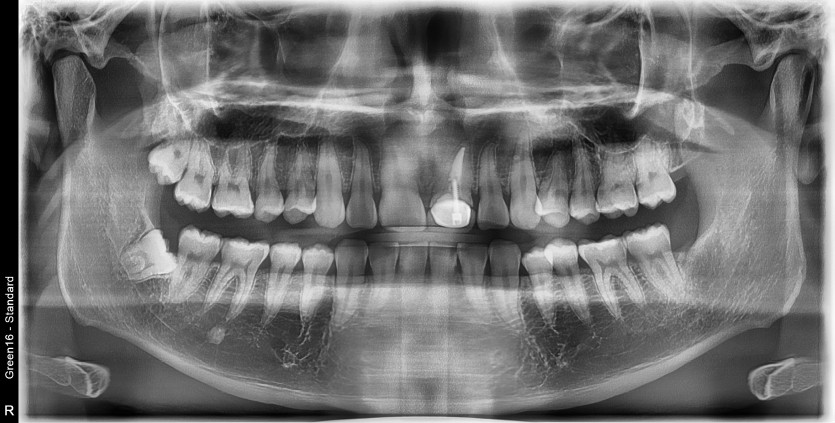

#18,48 사랑니 발치

구강외과 전문의가 당일 발치했습니다.